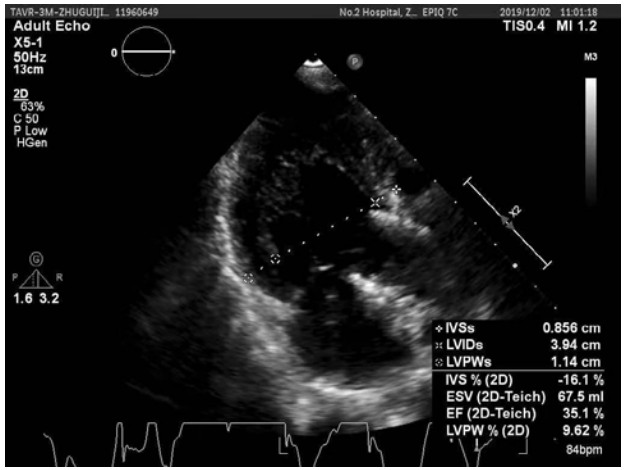

1 资料与方法患者, 女,71岁,30 kg,因“反复心悸胸闷13年余,加重1个月余”于2019年8月20日入院。体格检查:颈静脉怒张, 两肺呼吸音粗,两下肺可闻及明显湿啰音,心界向左扩大,胸骨右缘第二肋间可闻及4/6级舒张期叹气样杂音。实验室及辅助检查:心脏彩超(图 1)示主动脉瓣关闭不全伴重度反流,二尖瓣少中量反流,中度肺动脉高压;左室射血分数(left ventricular ejection fraction,LVEF)25%,左室舒张末容积(left ventricular end-diastolic volume,LVEDV)216 mL,左心房(left atrium,LA)4.81 cm。脑钠肽 > 5 000 pg/mL,肌钙蛋白I 0.13 ng/mL。Euroscore Ⅱ29.2%。入院诊断:主动脉瓣关闭不全伴重度反流,NYHA Ⅳ级;冠心病;短阵性室性心动过速。患者有主动脉瓣置换指征,鉴于外科手术高危,心脏团队经讨论后拟行TAVR术。

| 图 1 患者入院时心脏超声结果 |